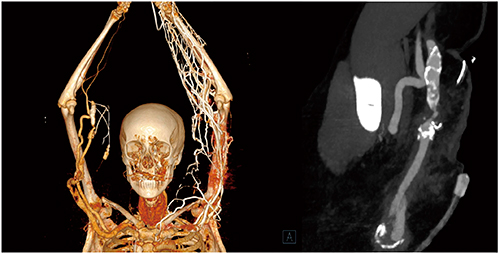

Case1では,70kVのLow kVイメージングにより造影剤量をさらに低減できた。20mLの造影剤を生理食塩水で50%希釈して使用したが,頸動脈および総腸骨動脈内の十分な造影効果が得られている(図1)。

図1 Case1:Low kVイメージングによる造影剤量の低減

(Whole-Body CT,70kV,造影剤量20mL)

この70kVでのLow kVイメージングは,ルーチンで使用可能である。Case2は,当院にて大動脈の人工血管および塞栓の評価に使用している4Dイメージングプロトコルで撮影した画像である(図2)。軸方向で80cmまでカバーできるが,造影剤量はわずか12mLであり,テストボーラスに使用する量をわずかに上回る程度であるため,ボーラストラッキングもテストボーラスも行っていない。最終的には70kVで12回のシャトルスキャンを行うが,ドイツの連邦放射線防護局が定める基準線量値の範囲内である。これは,CTにおける4Dイメージングの先端を行くものと言え,今後の診断体系も変わると言える。

図2 Case2:72歳,大動脈ステントグラフト挿入術後のエンドリーク

(70kV,造影剤量12mL)